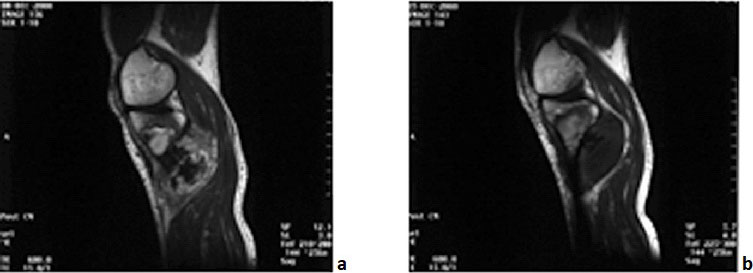

②对比增强CT或MRI:治疗区内原有的强化完全消失,形成非灌注区(图5-4)。

图5-4 骨肉瘤治疗前后增强MRI的变化

a.治疗前肿瘤内强化明显;b.治疗后治疗区内强化完全消失,边缘有一薄的强化带